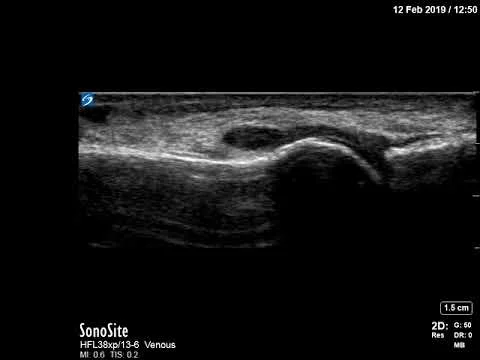

Knee effusion